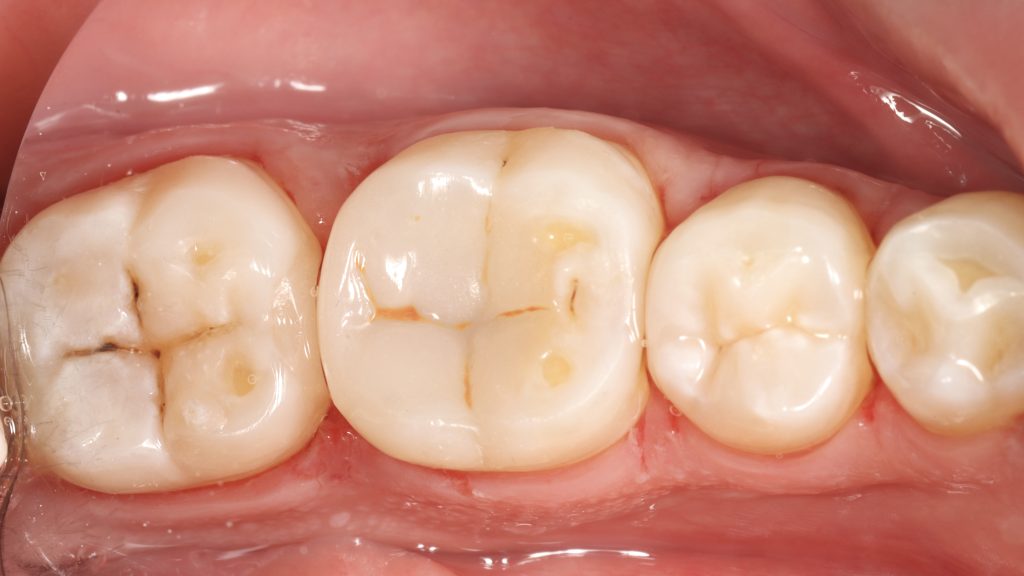

8.Restoring occlusal anatomy and tint added as fissure sealent then sandblasting by sodium bicarbonate to remove oxygen inhibition layer to prepare it for polishing steps.

9.A rubber twisted bur from Eve was used for polishing and goat hair for final glossing.

10.final situation after rubber dam removal and occlusal checking.